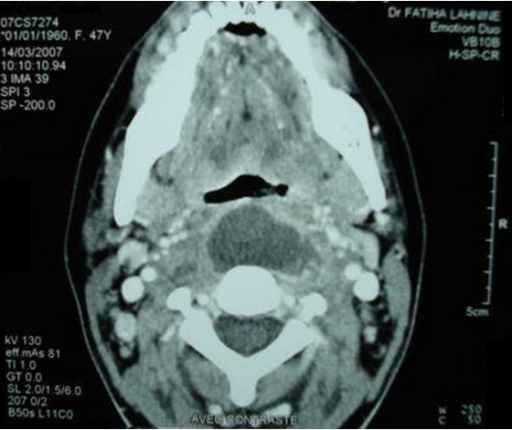

Retropharyngeal abscess in adults: five case reports and review of the literature. Harkani A, Hassani R, Ziad T, Aderdour L, Nouri H, Rochdi Y, Raji A - TheScientificWorldJournal (2011)

| actual | 05:21 6 ene 2022 | 512 × 430 (368 kB) | Rossdonaldson1 (discusión | contribs.) | Retropharyngeal abscess in adults: five case reports and review of the literature. Harkani A, Hassani R, Ziad T, Aderdour L, Nouri H, Rochdi Y, Raji A - TheScientificWorldJournal (2011) |